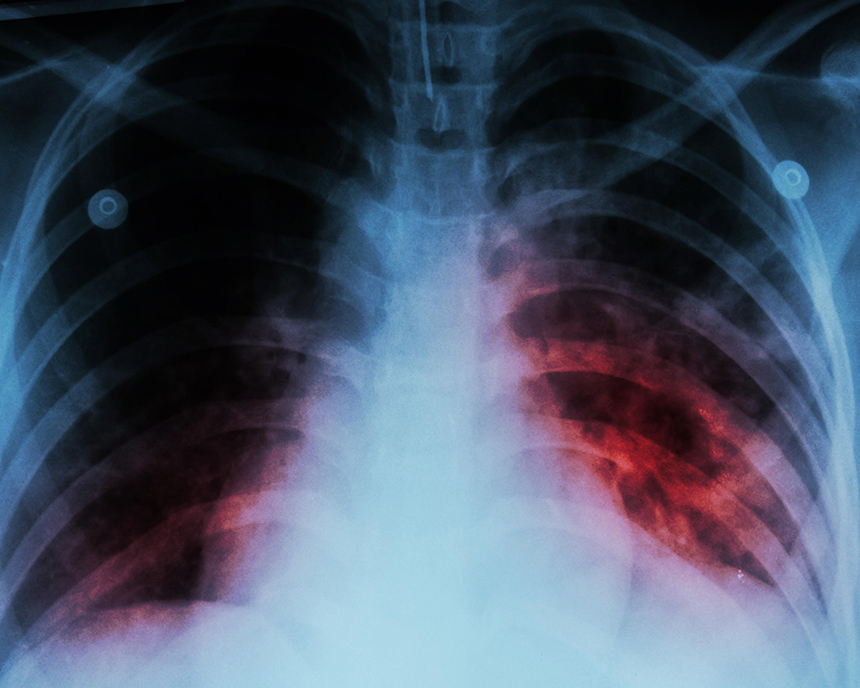

Tuberculosis. TB is arguably the world's leading cause of death from an infectious agent. The WHO estimates that 10.4 million new cases and 1.5 million deaths occur from TB each year (WHO 2016a). One-third of TB cases remain unknown to the health care system.